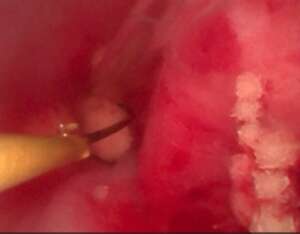

取り残しなどがないようにカメラで尿道内も確認していくと

このように尿道からいれている尿道カテーテルのよこに結石がのこっていました

細い内視鏡から鉗子をいれてその結石を取り除いていきます